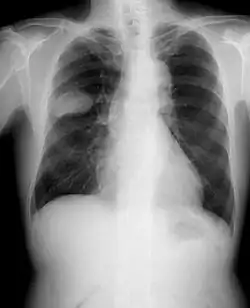

Cáncer de pulmón (lado derecho).

Radiografía simple de tórax

Radiografía de tórax mostrando un tumor canceroso en el pulmón izquierdo (en el recuadro).

En las radiografías simples de tórax se puede observar alguna anormalidad en casi el 98 % de los pacientes con un carcinoma broncogénico, y el 85 % son imágenes sugestivas para sospechar el diagnóstico por las alteraciones pulmonares distales (atelectasia), la existencia de adenopatías (ensanchamiento mediastínico) o detección de invasión de la pared torácica. La radiografía de tórax detecta elementos sospechosos en la mayoría de los pacientes con tumores pulmonares.[133]​ No se recomiendan las tomas radiológicas en serie para la detección temprana del cáncer de pulmón.[121]